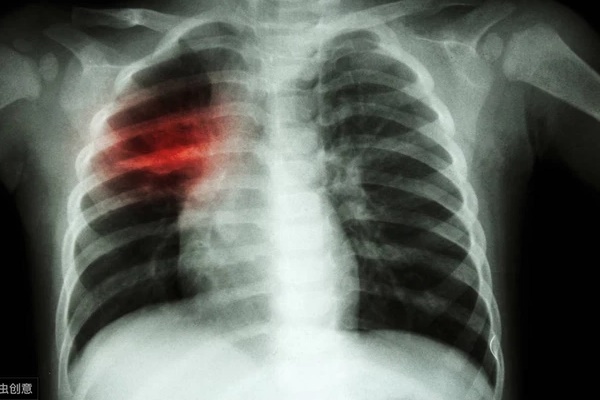

Kết quả xét nghiệm cho thấy ông Vương bị ung thư phổi giai đoạn cuối, ông Vương và gia đình đều không thể tin hay chấp nhận được, nhưng sự thật không thể thay đổi.

Theo hoàn cảnh của ông Vương, không quá bất ngờ khi kết quả khám là ung thư phổi, vì ông là người nghiện thuốc lá lớn tuổi, ngày nào cũng hút thuốc nhiều, độ tuổi nằm trong nhóm nguy cơ cao. Đồng thời, ông Vương cũng xuất hiện các triệu chứng của bệnh ung thư phổi - tức ngực và khó thở.